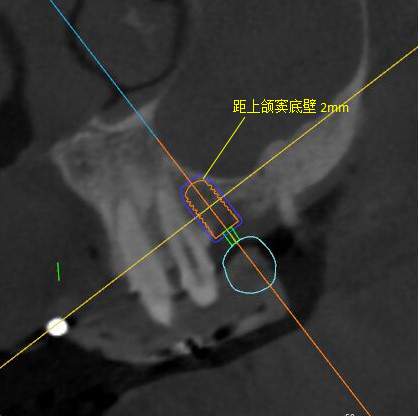

觀察患者CT,可看出患者有上頜竇粘膜囊腫,粘膜囊腫為竇內(nèi)腺體阻塞所致,視情況可有手術(shù)摘除和不予處理兩種方法,此次患者拒絕手術(shù)摘除,故需規(guī)避上頜竇位置。

根據(jù)患者CT顯示,使用種植導(dǎo)航軟件設(shè)術(shù)前手術(shù)方案??紤]到患者拒絕手術(shù)摘除上頜竇囊腫等因素,此次手術(shù)選用了Straumann骨水平4.10*8.0mm的植體,植體末端位點(diǎn)設(shè)計(jì)距上頜竇底壁2mm處的同時(shí)兼顧種植方向和修復(fù)間隙,來(lái)達(dá)到理想的效果。